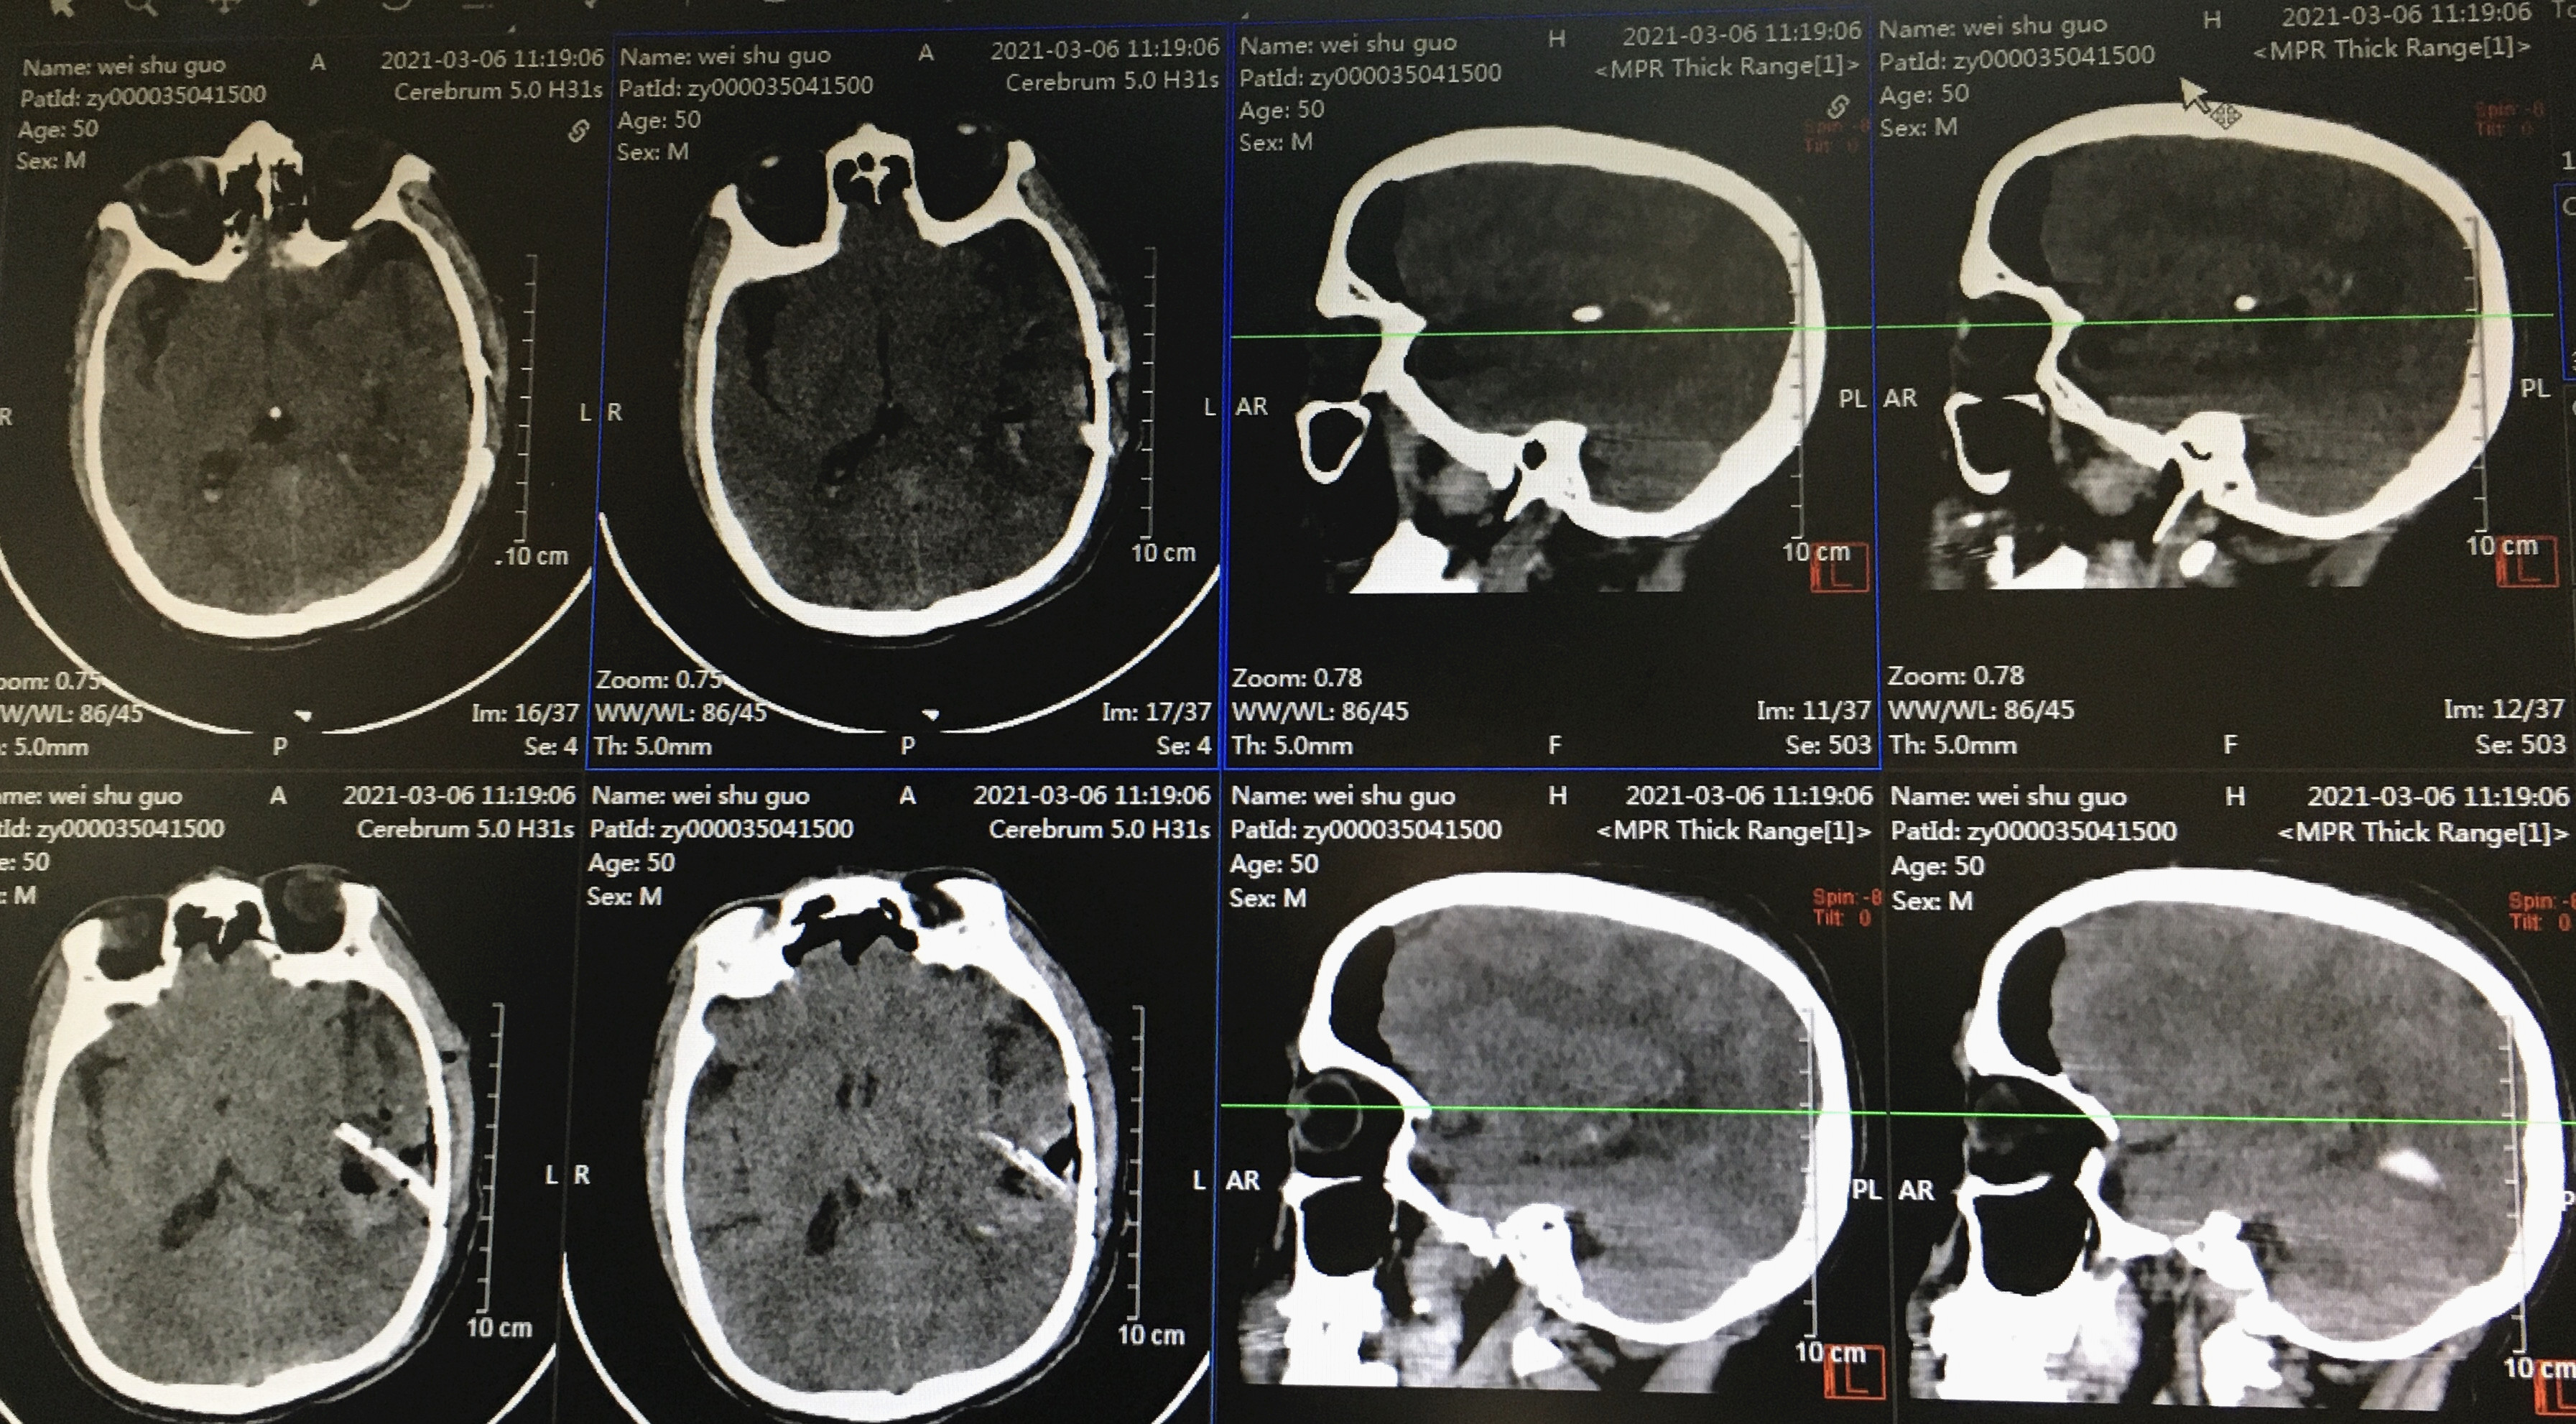

历经了2个多小时的精细手术,过程顺利。术后第2天,韦先生神志清醒,复查CT颅内出血完全清除,右侧肢体可自由活动,肌力恢复到正常水平,术后3天即可下床活动,2021年3月16日痊愈,步行出院。

术后复查出血已完全清除